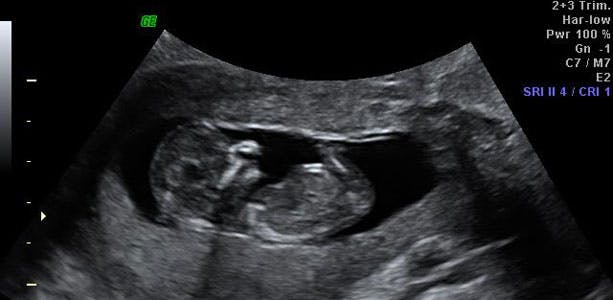

Gravid uge 13: Tid til at tage hul på 2. trimester

Med hensyn til størrelse kan du regne med, at det antal uger du er henne i din graviditet, svarer nogenlunde til den totale længde af din baby. I slutningen af denne uge kan man se de linjer på fingerspidserne, som kommer til at danne fingeraftrykkene. Alle knoglerne består stadig af brusk, men bliver løbende erstattet af ben. Barnet måler nu cirka 8,5 centimeter fra hoved til fod og vejer i slutningen af denne uge cirka 70 gram.